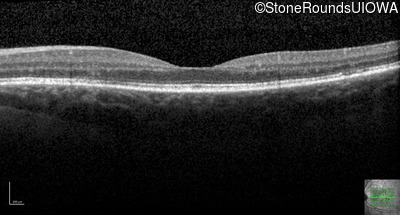

Optical Coherence Tomography - Left - 20/16 -1

Exemplar / OCT Stack

OCT Stack